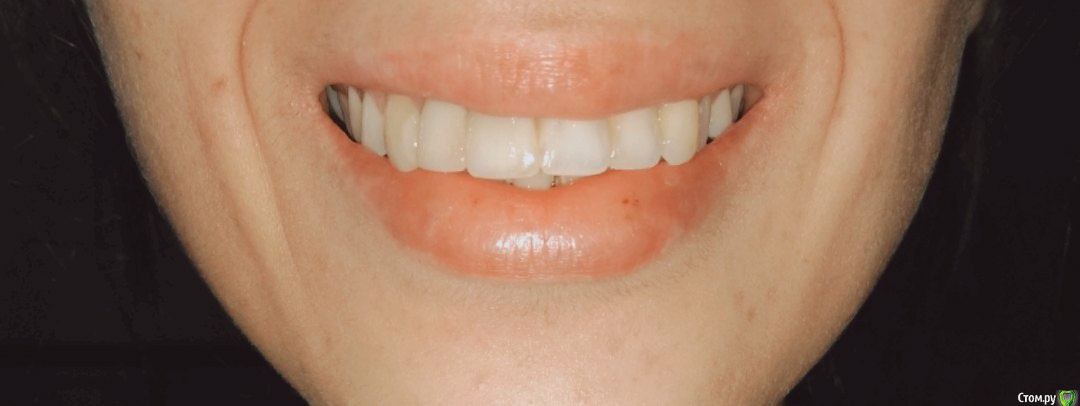

Добрый день. Носила брекеты 2года 3 месяца. Была небольшая скученность зубов (фото 1, начало лечения прилагается). Во время лечения брекетами очень сильно наклонились зубы вперед, еле закрывала рот. Удалили 8-ки с целью задвинуть их. Для этой цели ортодонт использовал маленькую пружинку которую ставил между зубами. В итоге-ничего не задвинулось,если не выдвинулось. Со временем, к снятию пришло ощущение, что нижняя челюсть не находит себе места, она висит, если зубы смыкать - то неудобно. Я тогда пошла сделала снимок рентген обоих суставов (фото 2 ). В заключении было сказано, что суставные щели внчс равномерны, суставные поверхности не изменены, при функциональных нагрузках визуализируется подвывих левого внчс. Я понесла это заключение ортодонту, он сказал что у меня все прекрасно, что этот подвывих есть у многих, и что он у меня скорее-всего был раньше. Я немного успокоилась. Но все таки ортодонта мучала мольбой чтоб исправил наклон передних зубов , но он уверял, что все хорошо, и что если сделать наклон, то корни передних зубов выйдут из десны и зубы будут держаться в слизистых... Это меня испугало. Центр нижней челюсти он не стал трогать, сказал, что это незаметно. И кстати нижние фронтальные зубы тоже  имеют наклон вперед. Из за этого при смыкании у меня нижние передние зубы упираются в верхние зубы под углом. Из-за этого чувствую при смыкании как передние зубы шатаются выдвигаясь еще больше наружу. Все таки меня уговорили снять брекеты, я надеялась, что после снятия мне будет легче и все устаканится. Я планировала беременность, поэтому больше не могла столько заниматься зубами (к слову, последний год, в связи с переездом мне пришлось ездить к ортодонту 12 часов на поезде в одну сторону, тратить 5000 пару раз в месяц на дорогу). Снятие было в ноябре, прошло 4 месяца. Меня стали мучать жуткие головные боли, шею тянет, позвоночнику некомфортно, в области обоих висков при открывании рта очень сильно выпирает и заметна подвижность какой-то шишечки, наверное это суставная головка. есть ощущение, что нижняя челюсть сильно задвинута назад, либо это верхняя слишком выдвинута, прикус у меня был нормальный, а теперь, кажется дистальный. Наклон передних зубов такой сильный, что помещается палец когда зубы сжаты. Лицо стало очень худым и изможденным, мне 26 лет, щеки впали сильно. Мышцы лица в области висков и щек очень сильно напряжены, постоянно какие то очень сильные похрустывания,Теперь начал болеть затылок,он начал хрустеть. жить стало просто невозможно. Какое-то состояние апатии, снижена концентрация внимании. Я не знаю к кому обратиться и что мне с этим делать.  Помогите, пожалуйста, как поступить